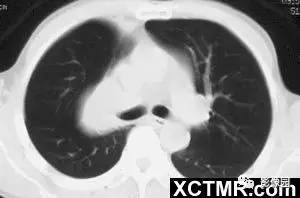

右肺上叶中央型肺癌1例CT影像表现

临床:男性,51岁。因咳嗽、咯痰5个月,伴左侧肢体乏力3个月入院。

CT平扫加增强扫描:右肺上叶见混杂密度肿块,大小6.5×6.5cm,边缘为厚环形较高密度软组织影,CT值43HU,注射造影剂后中度强化,CT值65HU,中央为低密度影,CT值24HU,注射造影剂后不强化。肿块周围为不张的右上肺组织包绕。注射造影剂后内可见杂乱的强化血管影。右肺上叶起始部中断。 医学百科网 | YxBaike.Com

CT诊断:右肺上叶占位,考虑中央型肺癌,并右肺上叶肺不张。 医学百科网 | YxBaike.Com